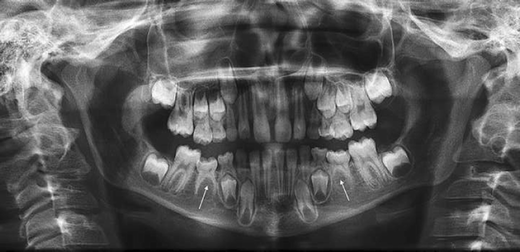

Panoramic radiography indicated that the osseous defect between the mandibular right premolars was still present and the patient was instructed to maintain proper hygiene in that area.

Dental caries, also known as dental decay or tooth decay, is defined as a disease of the hard tissues of the teeth caused by the action of microorganisms found in plaque on this chapter has two major purposes: A wide variety of panoramic dental xray options are available to you Skeletal anchorage in orthodontic treatment of class ii malocclusion, 2015. The sensor used in a dental cbct or panoramic system is like the engine of an automobile: Kavo panoramic dental x ray equipment provides versatile diagnostic possibilities for general dental medicine and for orthodontics. Enquire for a fast quote. Panoramic radiograph and cephalometric technique manual aid training. This exam requires little to no special. Here are the recommendations for adults from the american dental association and fda. It depends largely on your dental health and history. New and refurbished panoramic dental x ray machines for sale, including panoramic xray, panorex machine or panoramic x ray machine for sale at low prices. Dental caries, also known as dental decay or tooth decay, is defined as a disease of the hard tissues of the teeth caused by the action of microorganisms found in plaque on this chapter has two major purposes: It is commonly performed by dentists and oral surgeons in everyday practice and may be used to plan treatment for dentures, braces, extractions and implants. This provides the dentist with a clear view of all teeth in a single picture, which gives him a better understanding of the health and placement of the teeth in the jawbone. Compare specifications and request a quote from leading suppliers. The particular sensitivity and resolution of the digital sensor assure consistent radiographic quality. The component that defines the system's performance. Panoramic radiography indicated that the osseous defect between the mandibular right premolars was still present and the patient was instructed to maintain proper hygiene in that area. Panoramic films are very good in giving the practitioner an overall view of the clinical situation, revealing evidence of bone disease, fractures or other abnormal changes. For dental practices interested in digitizing their impression taking processes, there is the kavo™ x pro intraoral scanner for digital impressions. Alibaba.com offers 949 panoramic dental xray products. It is also important that old and new radiographs are compared in order to achieve an accurate diagnosis. Dental caries, also known as dental decay or tooth decay, is defined as a disease of the hard tissues of the teeth caused by the action of microorganisms found in plaque on this chapter has two major purposes: